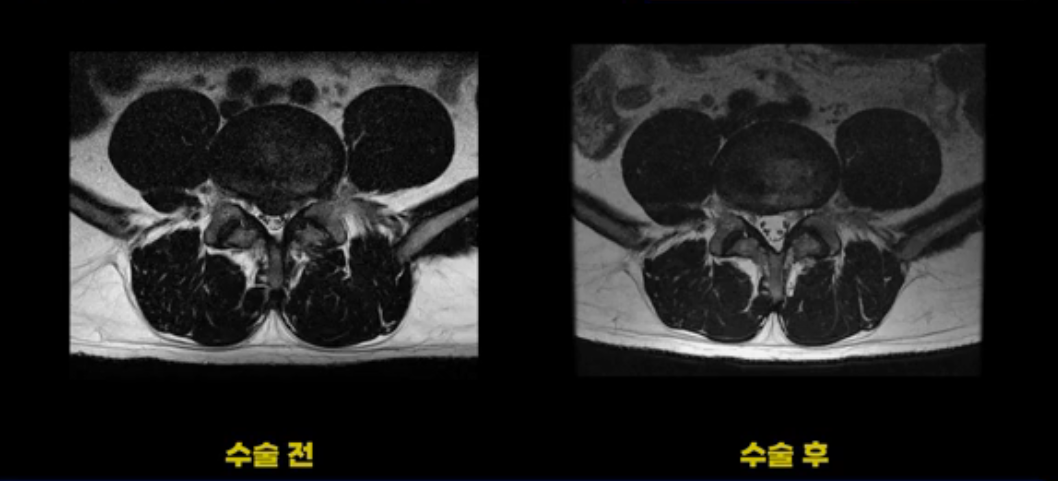

이 환자분은 디스크 파열 수술 후 3개월 정도 괜찮았다가 그 이후 점점 다리 저림과 통증이 다시 시작되어 수술 후 1년 정도부터는 거의 수술 전에 아팠던 정도까지 증상이 악화됩니다. 그런데 이분 수술 후 MRI를 보면 수술이 잘 돼서 깨끗합니다.

보시다시피 수술 전의 MRI와 비교해 보면 밀려 나온 디스크 수핵이 거의 대부분 깨끗이 제거되었습니다.

저희가 여러분께 계속해서 디스크든 협착이든 수술이 잘 되었는데도 계속 아프다면 그땐 근육 문제일 가능성이 매우 높다고 계속해서 말씀드리고 있지 않습니까? 이런 환자분이야말로 근육 문제를 의심해 봐야 합니다.